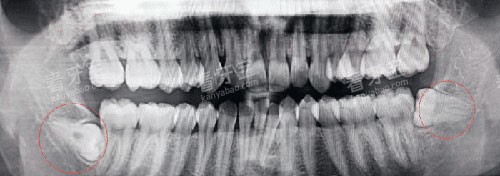

3.2 牙齿拔除价格

拔牙价格因牙齿类型和拔牙难度而异:

松动牙拔除(不含麻药):50元起/颗

上颌智齿拔除(简单/正位萌出):280元起/颗

下颌智齿拔除(简单/正位萌出):380元起/颗

阻生智齿拔除:500元起

但如果牙齿完全萌出,位置正常,拔除难度相对较小,费用通常在300-500元。

若智齿阻生,特别是低位阻生,价格可能会升至800-1500元。

复杂的阻生智齿拔除,如果需要切开牙龈、去骨等操作,费用可能达到1000-3000元。